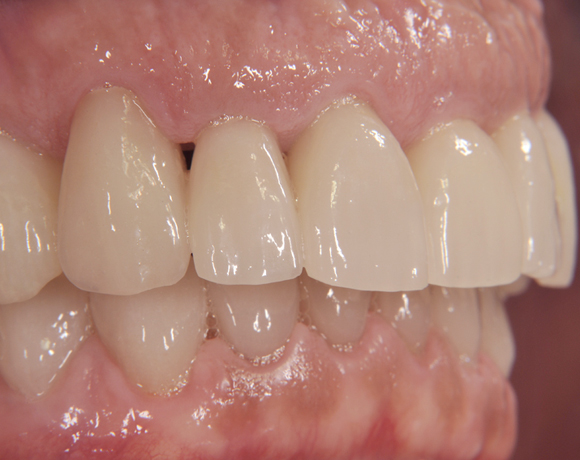

Der vorliegende Patientenfall zeigt eine komplette Neuversorgung der vorhandenen Metallkeramikkronen mit vollkeramischen Restaurationen. Zusätzlich wurde im Oberkiefer die Zahnreihe mit zwei Implantaten, für die fehlenden Molaren, ergänzt. Da keine ausreichende Knochenhöhe vorhanden war wurde ein interner Sinuslift geplant.